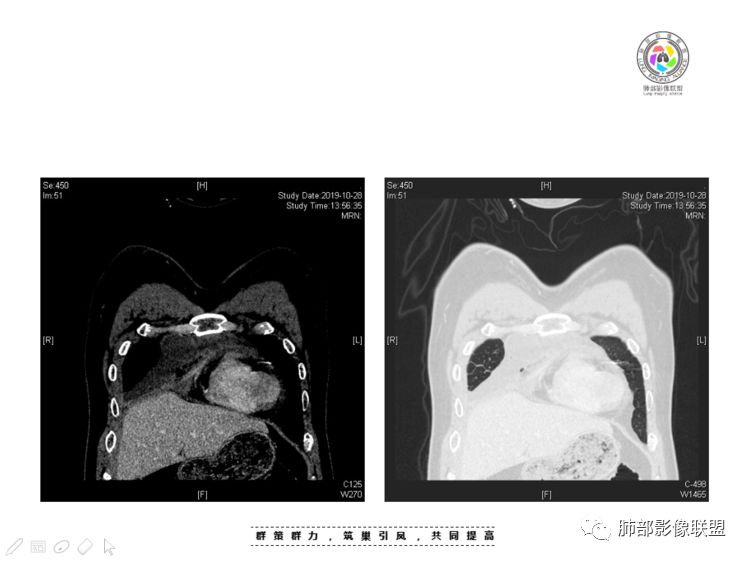

南边:大家看看前纵隔的病灶,符合肿瘤吗脂肪,周围密度增高

三个石头:比较散;像炎症的蔓延生长南边:是,这些看着心里不踏实觉得把这个纳入肿瘤去考虑是否合适总觉得边缘收缩的、散在的朝周围蔓延;中央还跨过脂肪,朝对侧胸膜蔓延把这个与囊性病变连到一起去考虑是否还需要斟酌一下因为这个就方向差异大了南边:连在一起,囊实性,边界不清,自然考虑恶性:如果独立,囊张力高、边界清楚,间隔,自然朝良性考虑:

Coke with ice:囊性部分考虑包裹性积液?南边:不是积液;有间隔;张力高;而且位置有些特殊

我认为囊张力高,积液中的气体均在周围,外侧、下方,囊内有间隔:各腔密度不一致;提示:囊腔属于前纵隔,不是包裹性积液;现在的问题:囊腔与内侧的病灶是否是一体的

南边:我总觉得这个纵隔内不像是一个肿块的改变,扁平,周围蔓延:有符合炎性的的特点,或者肿瘤的侵犯;但是肿瘤的侵犯,不大符合,实性部位的边缘过于柔和,没有毛糙的侵犯边缘。